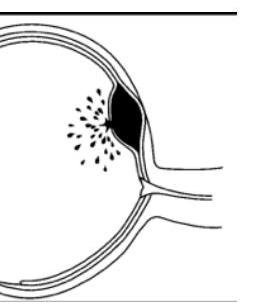

# EVC HEMORRÁGICO ## DEFINICIÓN Tal como se ha planteado en el documento de EVC Isquémico, estos eventos corresponden a un síndrome clínico caracterizado por el **rápido desarrollo de síntomas y signos correspondientes a un déficit neurológico focal** y que persisten por más de 24 horas, sin otra causa aparente distinta a la de origen vascular, que además se visualiza por estudios de imagen.  El EVC de origen hemorrágico corresponde aproximadamente al 20% de todos los EVC que se presentan, siendo la causa más frecuente la **hemorragia subaracnoidea**, secundaria a un traumatismo, aunque también puede presentarse secundaria a una ruptura aneurismática, con menor frecuencia. ## LOCALIZACIÓN ## Ganglionar 48 % ## Tálamo 23 % ## Lobar 15 % Puente 6% ## Cerebelo 5% Núcleo Caudado 3% ## Etiología | Hipertensión Arterial | Ganglios basales, tálamo, lobar, puente, cerebelo | | :--: | :-- | | Malformaciones vasculares | Cerebelo, intraventricular, lobar, puente, subaracnoidea | | Aneurismas Cerebrales | **HEMORRAGIA SUBARACNOIDEA** (no provocan hemorragia parenquimatosa) | | Angiopatía Amiloide | (debilidad de los vasos, se degenera la íntima media) - lobar, subaracnoidea | | Coagulopatías | Lobar, subaracnoidea, cerebelo | | Tumores | Depende de localización | | Fármacos y drogas | Lobar, subaracnoidea, intraventricular | # EPIDEMIOLOGÍA FACTORES MODIFICABLES - HAS - DM - Tabaquismo y alcoholismo - Cardiopatías congestivas - Valvulopatías, FA, IAM - Dislipidemia - Sedentarismo y obesidad - Traumatismos - Aneurismas - Malformaciones Arteriovenosas - Angiopatía Amiloide - Anticoagulantes. ## FACTORES DE RIESGO PARA ANEURISMA - Edad: 40-65 años $\rightarrow$ 80 % - Femenino 3:2 Masculino - HTA - Tabaco - Alcohol-Cocaína ## FACTORES NO MODIFICABLES - Edad avanzada - Género masculino - Historia familiar de EVC # HEMORRAGIA SUBARACNOIDEA Ocurre cuando la **RUPTURA VASCULAR** se extravasa **HACIA EL ESPACIO SUBARACNOIDEO** - La sangre se disemina hacia las cisternas basales y el espacio subaracnoideo ## ETIOLOGÍA 1. **ANEURISMAS SACULARES** (70-85%) que tienen forma de saco. Defectos congénitos de pared muscular y elásticas de arterias o adquiridos a través de cambios degenerativos de pared arterial. **Fuerza de rozamiento** (Stress) hemodinámico y herencia se han implicado en el desarrollo o ruptura del aneurisma. 2. MAVs - pueden reventarse subaracnoidea, pero habitualmente son parenquimatosas. 3. TCE 4. Otros: disecciones, micóticos  ## CLÍNICA - Es de inicio **ABRUPTO** con una **CEFALEA INTENSÍSIMA**. - DESCRITA COMO **LA PEOR DE SU VIDA**. - Seguida de rigidez nucal o signos meníngeos - Fotofobia, náuseas, vómitos - Parálisis de nervios craneales y déficit motor Hemorragia Subhialoideas Ya que el nervio óptico es una expansión del SNC.  (c) Copyright 2021-2022 Joyas ENARM - Todos los derechos reservados - # DIAGNÓSTICO ## GOLD STANDARD: Angiografía Cerebral Selectiva con Sustracción Digital - Permite identificar el aneurisma y al ser este la causa más frecuente será el ideal. ## 1ra elección: TOMOGRAFÍA COMPUTARIZADA - Es el estudio más indicado por la accesibilidad - Si la tomografía es negativa y tiene datos de aneurisma, lo más probable es que solamente haya goteado. - Se sugieren los otros estudios para vigilancia. ## RESONANCIA MAGNÉTICA - Es el estudio de elección, pero en caso de no contar con ella se utiliza TAC ## PUNCIÓN LUMBAR - Si la Tomografía Computarizada resulta negativa, ante la sospecha se debe realizar **PUNCIÓN LUMBAR**. ## ESCALAS AUXILIARES Estas escalas solamente aplican para casos en los que la hemorragia es subaracnoidea y exclusivamente provocada por rupturas aneurismáticas. ## ESCALA DE FISHER I Sin evidencia de sangrado en cisternas ni ventrículos II - **SANGRE DIFUSA** fina - Capa **MENOR 1 mm** en cisternas medida verticalmente - **COÁGULO** grueso cisternal III - Su tamaño es **MAYOR 1 mm** en cisternas medida verticalmente IV $\cdot$ **HEMATOMA INTRAPARENQUIMATOSO** - Hemorragia Intraventricular - Puede o no haber sangrado difuso  ESCALA DE HUNT Y HESS | $\mathbf{1}$ | Paciente asintomático, dolor de cabeza leve, ligera rigidez de la nuca | | :-- | :-- | | $\mathbf{2}$ | Dolor de cabeza moderado - fuerte, rigidez de la nuca, sin déficit neurológico fuera de la parálisis del nervio craneal | | $\mathbf{3}$ | Somnolencia, confusión, obnubilación, déficit neurológico focal leve. | | $\mathbf{4}$ | Estupor, hemiparesia moderada - severa, rigidez de descerebración temprana | | $\mathbf{5}$ | Coma profundo, signos de descerebración. | # TRATAMIENTO ## PREVENIR RESANGRADO - Será importante durante las primeras 48 horas. - Mantener TA Sistólica por debajo de 150 mmHg hasta realizar clipaje o embolización PREVENIR VASOESPASMO (la complicación más grave) Y DETERIORO NEUROLÓGICO Esto puede ocurrir a los 5-7 días. Administrar BLOQUEADORES CANALES DE CALCIO IV: - 1ra elección **NIMODIPINO** (Estrictamente por SNG 2 tabletas cada 4 horas) - El nimodipino IV está contraindicado porque aumenta la mortalidad ya que genera hipotensión sanguínea que puede condicionar una falla en la autorregulación. - Otros: Amlodipino, Nifedipino, Verapamilo - Soluciones IV ## DISMINUIR PRESIÓN INTRACRANEAL - Mantener posición semi-Fowler - Tratar la hidrocefalia con ventriculostomía ## TRATAMIENTO DEFINITIVO - OCLUSIÓN VASCULAR O QUIRÚRGICA CON CLIP  # HEMORRAGIA INTRAPARENQUIMATOSA Son las hemorragias que se producen dentro del encéfalo como consecuencia de la ruptura de un vaso profundo, ya sea arterial o venoso. - La parenquimatosa no aneurismática - Es mayor en asiáticos, es intermedia en negros y es menor en caucásicos - MEXICO mayor que USA en 20% - 26 % de los EVC Las más graves son las **HEMORRAGIAS DEL CEREBELO**, rápidamente crece el hematoma y comprime ## Factores de riesgo: - **HIPERTENSIÓN ARTERIAL** - La más importante - Condición predisponente más importante - Factor de riesgo modificable - El control de la HTA reduce el riesgo de HC en 50% - El cambio primario es el daño a la capa media de la pared del vaso. - Alcohol - Induce hipertensión esencial primaria - Bebedores ligeros hasta 414 ml / mes - Bebedores moderados hasta 1.2 L/mes - Bebedores intensos mayor a 1.2 L /mes - Colesterol - La dislipidemia es un factor de riesgo. Disminuir los lípidos. - En Hemorragia cerebral si te pasas, puedes favorecer - Debilitar el endotelio favoreciendo el desarrollo de hemorragia - **MENOR a 160 mg / dL** - Ácido Acetilsalicílico # CLÍNICA ## CEFALEA - 50% de los casos - Distorsión y tracción de meninges y vasos sanguíneos - Aumento generalizado de la PIC - Irrupción sanguínea a los ventrículos o al espacio subaracnoideo - Los hematomas pequeños puramente parenquimatosos no suelen producir cefalea. ## ALTERACIÓN DEL ESTADO DE ALERTA - Se asocia con la extensión y localización - El estado de coma fue más frecuente con hemorragia pontina - El estado de conciencia al ingreso es un factor pronóstico. Excepto en hemorragia **TALÁMICA**. - Todo lo que lesione el **TÁLAMO CAUSARÁ HIPERSOMNIA**. ## VÓMITO - Útil en el dx diferencial entre infarto y hemorragia - En el infarto 2% y hemorragia 48% ## CONVULSIONES - 6-15% ## DIAGNÓSTICO ## ESTUDIO DE ELECCIÓN: TOMOGRAFÍA COMPUTARIZADA - En la etapa aguda es el estudio de mayor sensibilidad - En la etapa subaguda y crónica es menos preciso | Etapa Hiperaguda ( 0-4 horas) | Lesión hiperdensa de color blanco | | :--: | :-- | | Etapa Aguda (5-72 horas) | Lesión hiperdensa (blanca) con mínimo contorno hipodenso (de color negro) | | Etapa Subaguda (4-21 días) | Lesión hiperdensa con máximo contorno hipodenso (que puede captar el contraste) | | Etapa Crónica (+21 días) | Lesión Isodensa (color gris) | # TRATAMIENTO - CONTROL DE TA: Labetalol e Hidralazina - Asistencia Ventilatoria - Posición Semi-Fowler - Intervención Qx si presenta efecto de masa. ## AUTORREGULACIÓN CEREBRAL - Capacidad de mantener la perfusión del cerebro, vasodilatando o vasoconstriñendo. - PAM +120 pierden la autorregulación - Las cerebrales posteriores prácticamente no tienen - Las cerebrales medias y anteriores se regulan  Hematoma Intraparenquimatoso Intracerebral # Hemorragias Intracraneales Hemorragia intraparenquimatosa Ruptura súbita de arteria intracerebral ## Etiología - HTA en < 55 años - Angiopatía amiloidea en > 55 años HTA es el principal factor de riesgo Hematoma epidural Lesión de la meníngea media por trauma Hay pérdida transitoria de memoria que se recupera para volver a sufrir deterioro del estado de alerta (lucidez intermedia) Clínica derivada de herniación uncal Toma forma biconvexa Hemorragia subaracnoidea Puede ser traumática o espontánea Frecuentemente por aneurismas Factores de riesgo - Tabaquismo (mujeres) - Alcoholismo - HTA Pueden presentar cefalea, náusea, vómito, **sx** meníngeo Hematoma subdural Ruptura de venas puente entre cerebro y senos durales Etiología traumática Toma forma de media luna